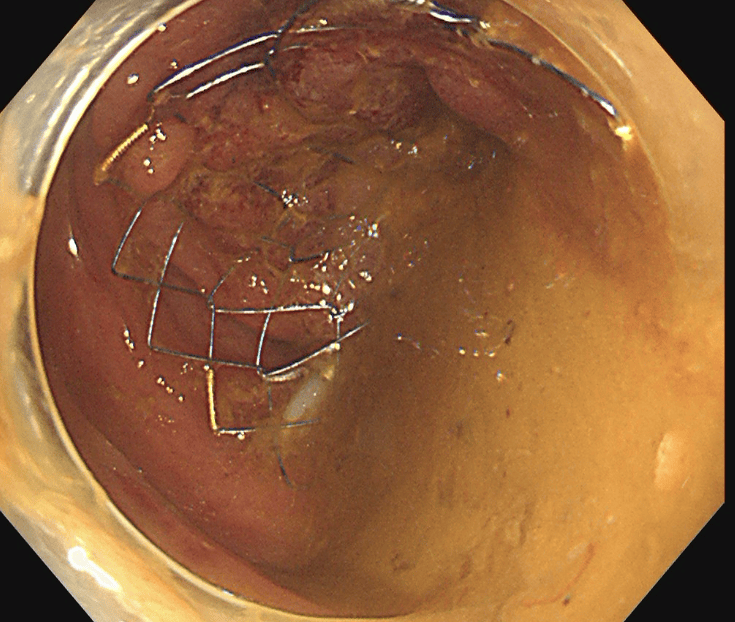

閉塞性大腸がんに対する大腸ステント治療

大腸がんが進行し腸が詰まってしまう閉塞性大腸がん(大腸がん腸閉塞)に対する治療です。従来は人工肛門を造設して対処していましたが、人工肛門はケアの負担やにおいに対する不安などからQOL(生活の質)低下が避けられません。そのため当院ではステントと言われるメッシュ構造の金属製の網を用いて詰まりを解消し、人工肛門を回避する治療を行っています。大腸ステント治療は緩和治療を目的に行う場合と根治手術前に全身状態の回復を目的として行う場合があります。

ステント留置後(内視鏡画像)